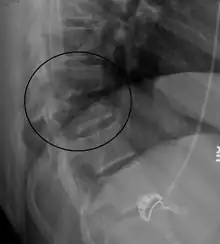

Chance fracture

A Chance fracture is a type of vertebral fracture that results from excessive flexion of the spine.[8][9] Symptoms may include abdominal bruising (seat belt sign), or less commonly paralysis of the legs.[4][10] In around half of cases there is an associated abdominal injury such as a splenic rupture, small bowel injury, pancreatic injury, or mesenteric tear.[3][5] Injury to the bowel may not be apparent on the first day.[11]

| A Chance fracture of T10 and fracture of T9 due to a seatbelt during an MVC. | |

The cause is classically a head-on motor vehicle collision in which the affected person is wearing only a lap belt.[2] Being hit in the abdomen with an object like a tree or a fall may also result in this fracture pattern.[12][10] It often involves disruption of all three columns of the vertebral body (anterior, middle, and posterior).[7][6] The most common area affected is the lower thoracic and upper lumbar spine.[6] A CT scan is recommended as part of the diagnostic work-up to detect any potential abdominal injuries.[5] The fracture is often unstable.[1]

On plain X-ray, a Chance fracture may be suspected if two spinous processes are excessively far apart.[10]